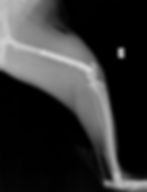

診断は主にレントゲン検査で行います。

どの位置で折れているか

骨のズレはどれくらいか

関節に影響していないか

その他の骨折などはないか

を確認し、治療方針を決めます。

プレートやピンなどの金属を使って骨を固定

正しい位置に戻し、しっかり癒合させる

という処置を行います。